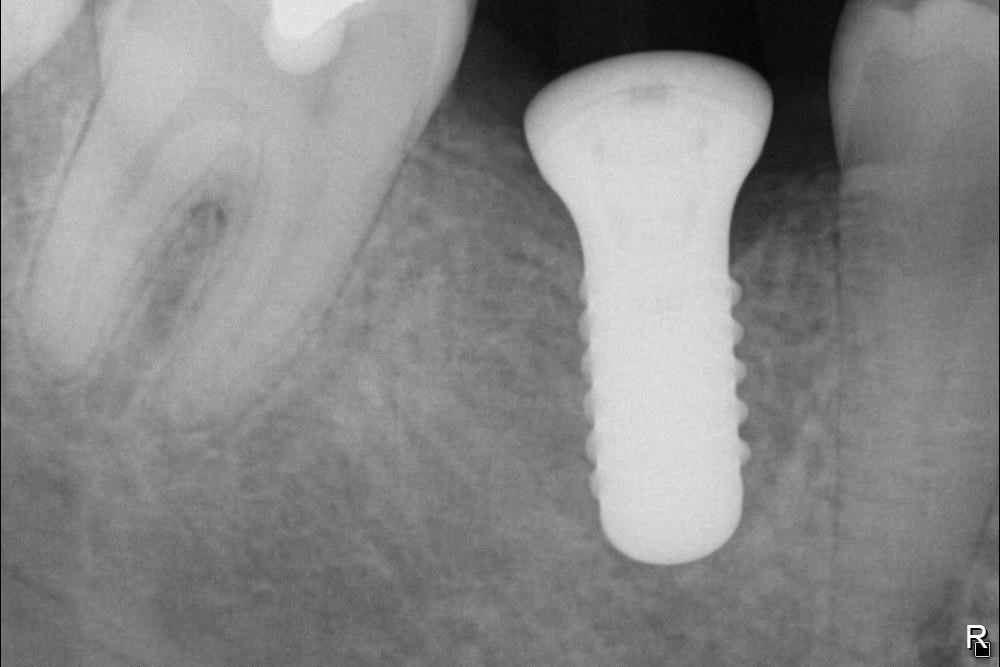

Implantát v postranním úseku chrupu.